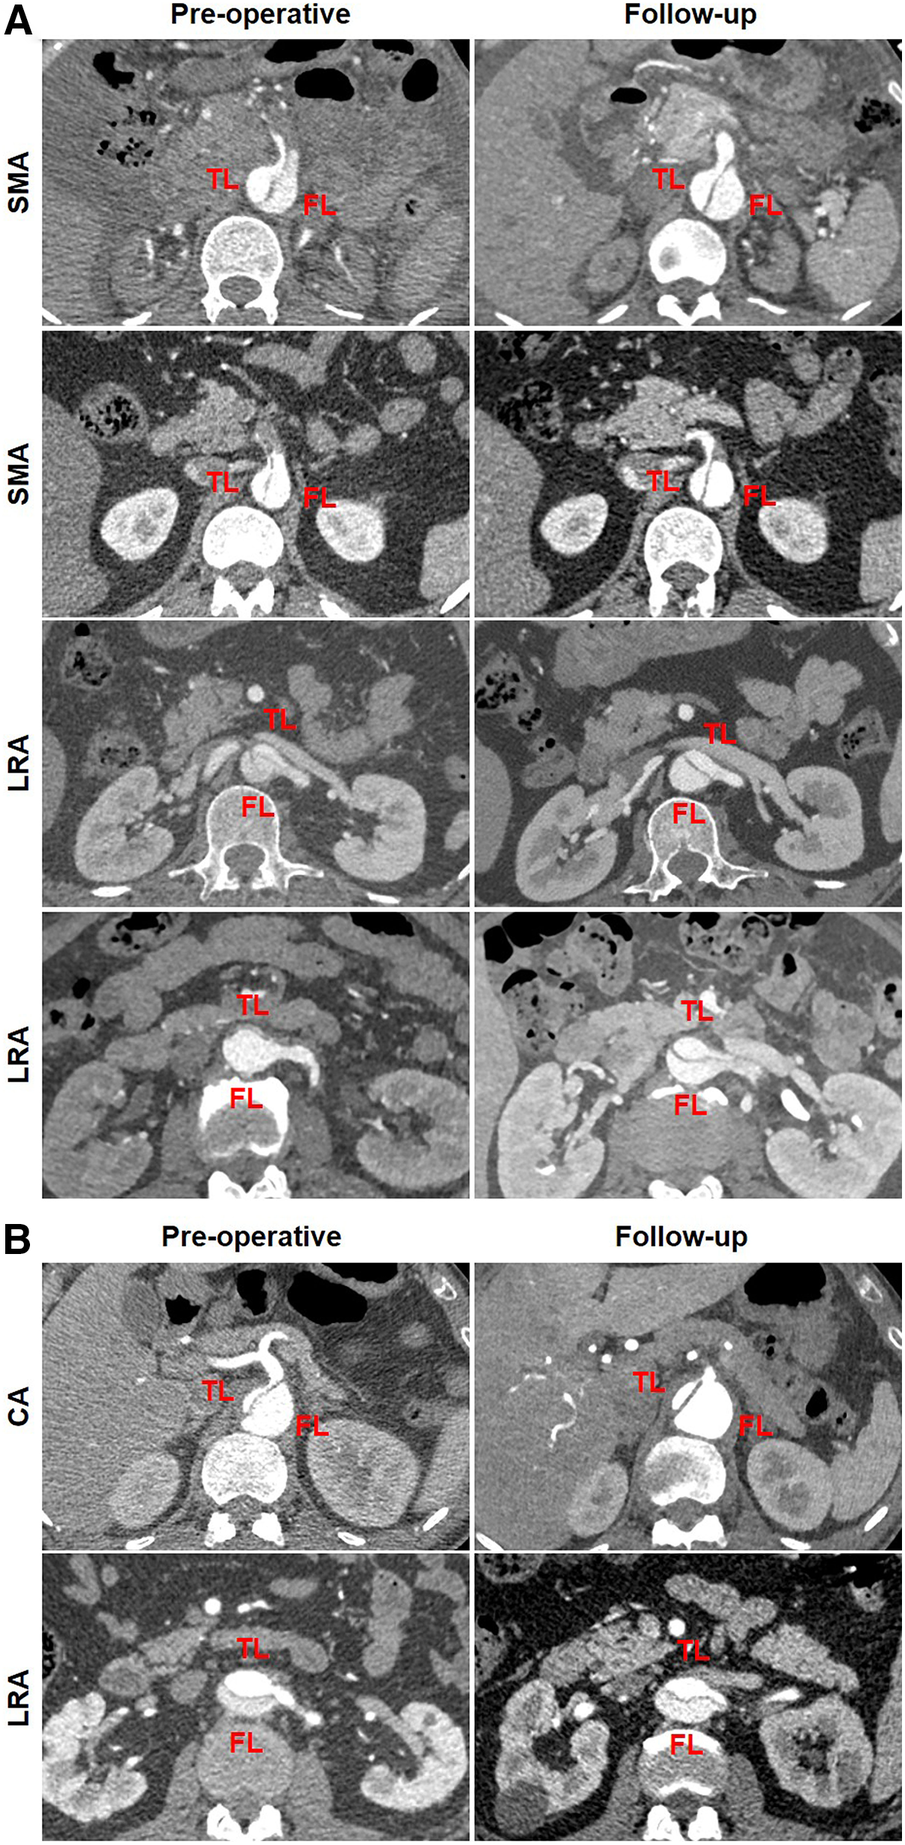

A total of 21 patients were divided into two groups according to the changes in TL diameters at the abdominal aorta: TL growth (n = 7) and TL stabilization/shrinkage (n = 14). Representative CT images of two categories of TL growth and TL stabilization/shrinkage are shown in Figure 6A,B, respectively. CT images in the horizontal plane were illustrated at the level of LRA and iliac bifurcation, and CT images in the coronal plane were obtained at the abdominal aorta. A 52-year-old man diagnosed with TBAD had a preoperative TL ratio at iliac bifurcation of 34.6% (cutoff of >21.0%). At 12 months after TEVAR, his abdominal TL diameter was maintained stable between pre-procedure and follow-up (12.4 vs. 13.8 mm at LRA level and 10.4 vs. 10.7 mm at aortic bifurcation) (Figure 6A). A 64-year-old man diagnosed with TBAD showed a TL ratio at aortic bifurcation of 11.1% (cutoff of <21.0%). One month later, his abdominal TL diameter was markedly enlarged from pre-procedure to follow-up (2.8 vs. 10.8 mm at LRA level and 2.1 vs. 11.7 mm at aortic bifurcation) (Figure 6B).

Figure 6

Abdominal TL growth or stabilization after TEVAR with the Castor stent graft. (A) The initial TL ratio at iliac bifurcation was measured as 46.6%, which exceeded a cutoff prediction value of 21.0%. Abdominal TL diameter did not alter at the 12-month follow-up. (B) When the initial TL ratio at iliac bifurcation was 10.5% below the cutoff value of 21.0%, abdominal TL diameter was significantly increased at 1-month follow-up. TEVAR, thoracic endovascular aortic repair; TL, true lumen.

Table 6 summarizes the abdominal aortic branch perfusion pattern preoperatively and at follow-up. Abdominal aortic branches were mostly perfused by a TL, including the CA (65.4%, 17/26), SMA (84.0%, 21/25), LRA (60.0%, 15/25), and RRA (60.0%, 15/25). Renal artery perfusion was frequently involved in dissection with 40% of the LRA or RRA by a FL or BL. Approximately 3.9% of the branches (4/102) were characterized as positive remodeling, including two SMA and two LRA. Negative remodeling was seen in 1.9% of the branches (2/102) consisting of one CA and one LRA. The majority of the branch perfusions (94.1%, 96/102) did not change after TEVAR. There were no statistical differences in TL, FL, and BL origination between pre-procedure and follow-up. Positive branch remodeling is illustrated in Figure 7A. Two SMAs were in transit from BL preoperatively to TL at follow-up. One LRA switched from BL preoperatively to TL at follow-up. One LRA was altered from FL preoperatively to BL at follow-up. Negative branch remodeling is indicated in Figure 7B. The CA changed from TL to BL after TEVAR, and LRA switched from TL to BL after TEVAR.

Figure 7

Abdominal aortic branch remodeling after TEVAR. (A) In the patterns of positive remodeling, the SMA was perfused by BL preoperatively and by TL at follow-up, one LRA was perfused by BL preoperatively and by TL at follow-up, and one LRA was perfused by FL preoperatively and by BL at follow-up. (B) In the patterns of negative remodeling, the CA was perfused by TL preoperatively and BL at follow-up, and the LRA was perfused by TL preoperatively and BL at follow-up. BL, bilateral lumen; CA, celiac artery; FL, false lumen; LRA, left renal artery; RRA, right renal artery; SMA, superior mesenteric artery; TEVAR, thoracic endovascular aortic repair; TL, true lumen.